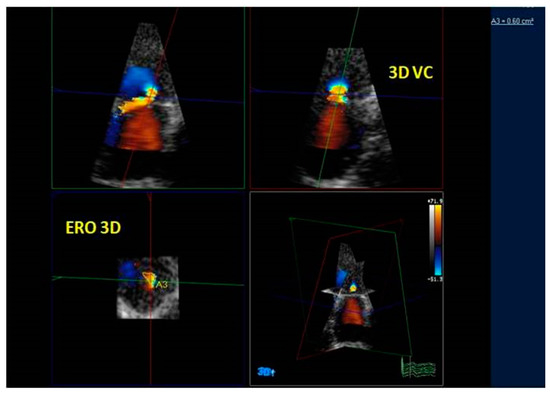

3.3. Quantification of Mitral Regurgitation